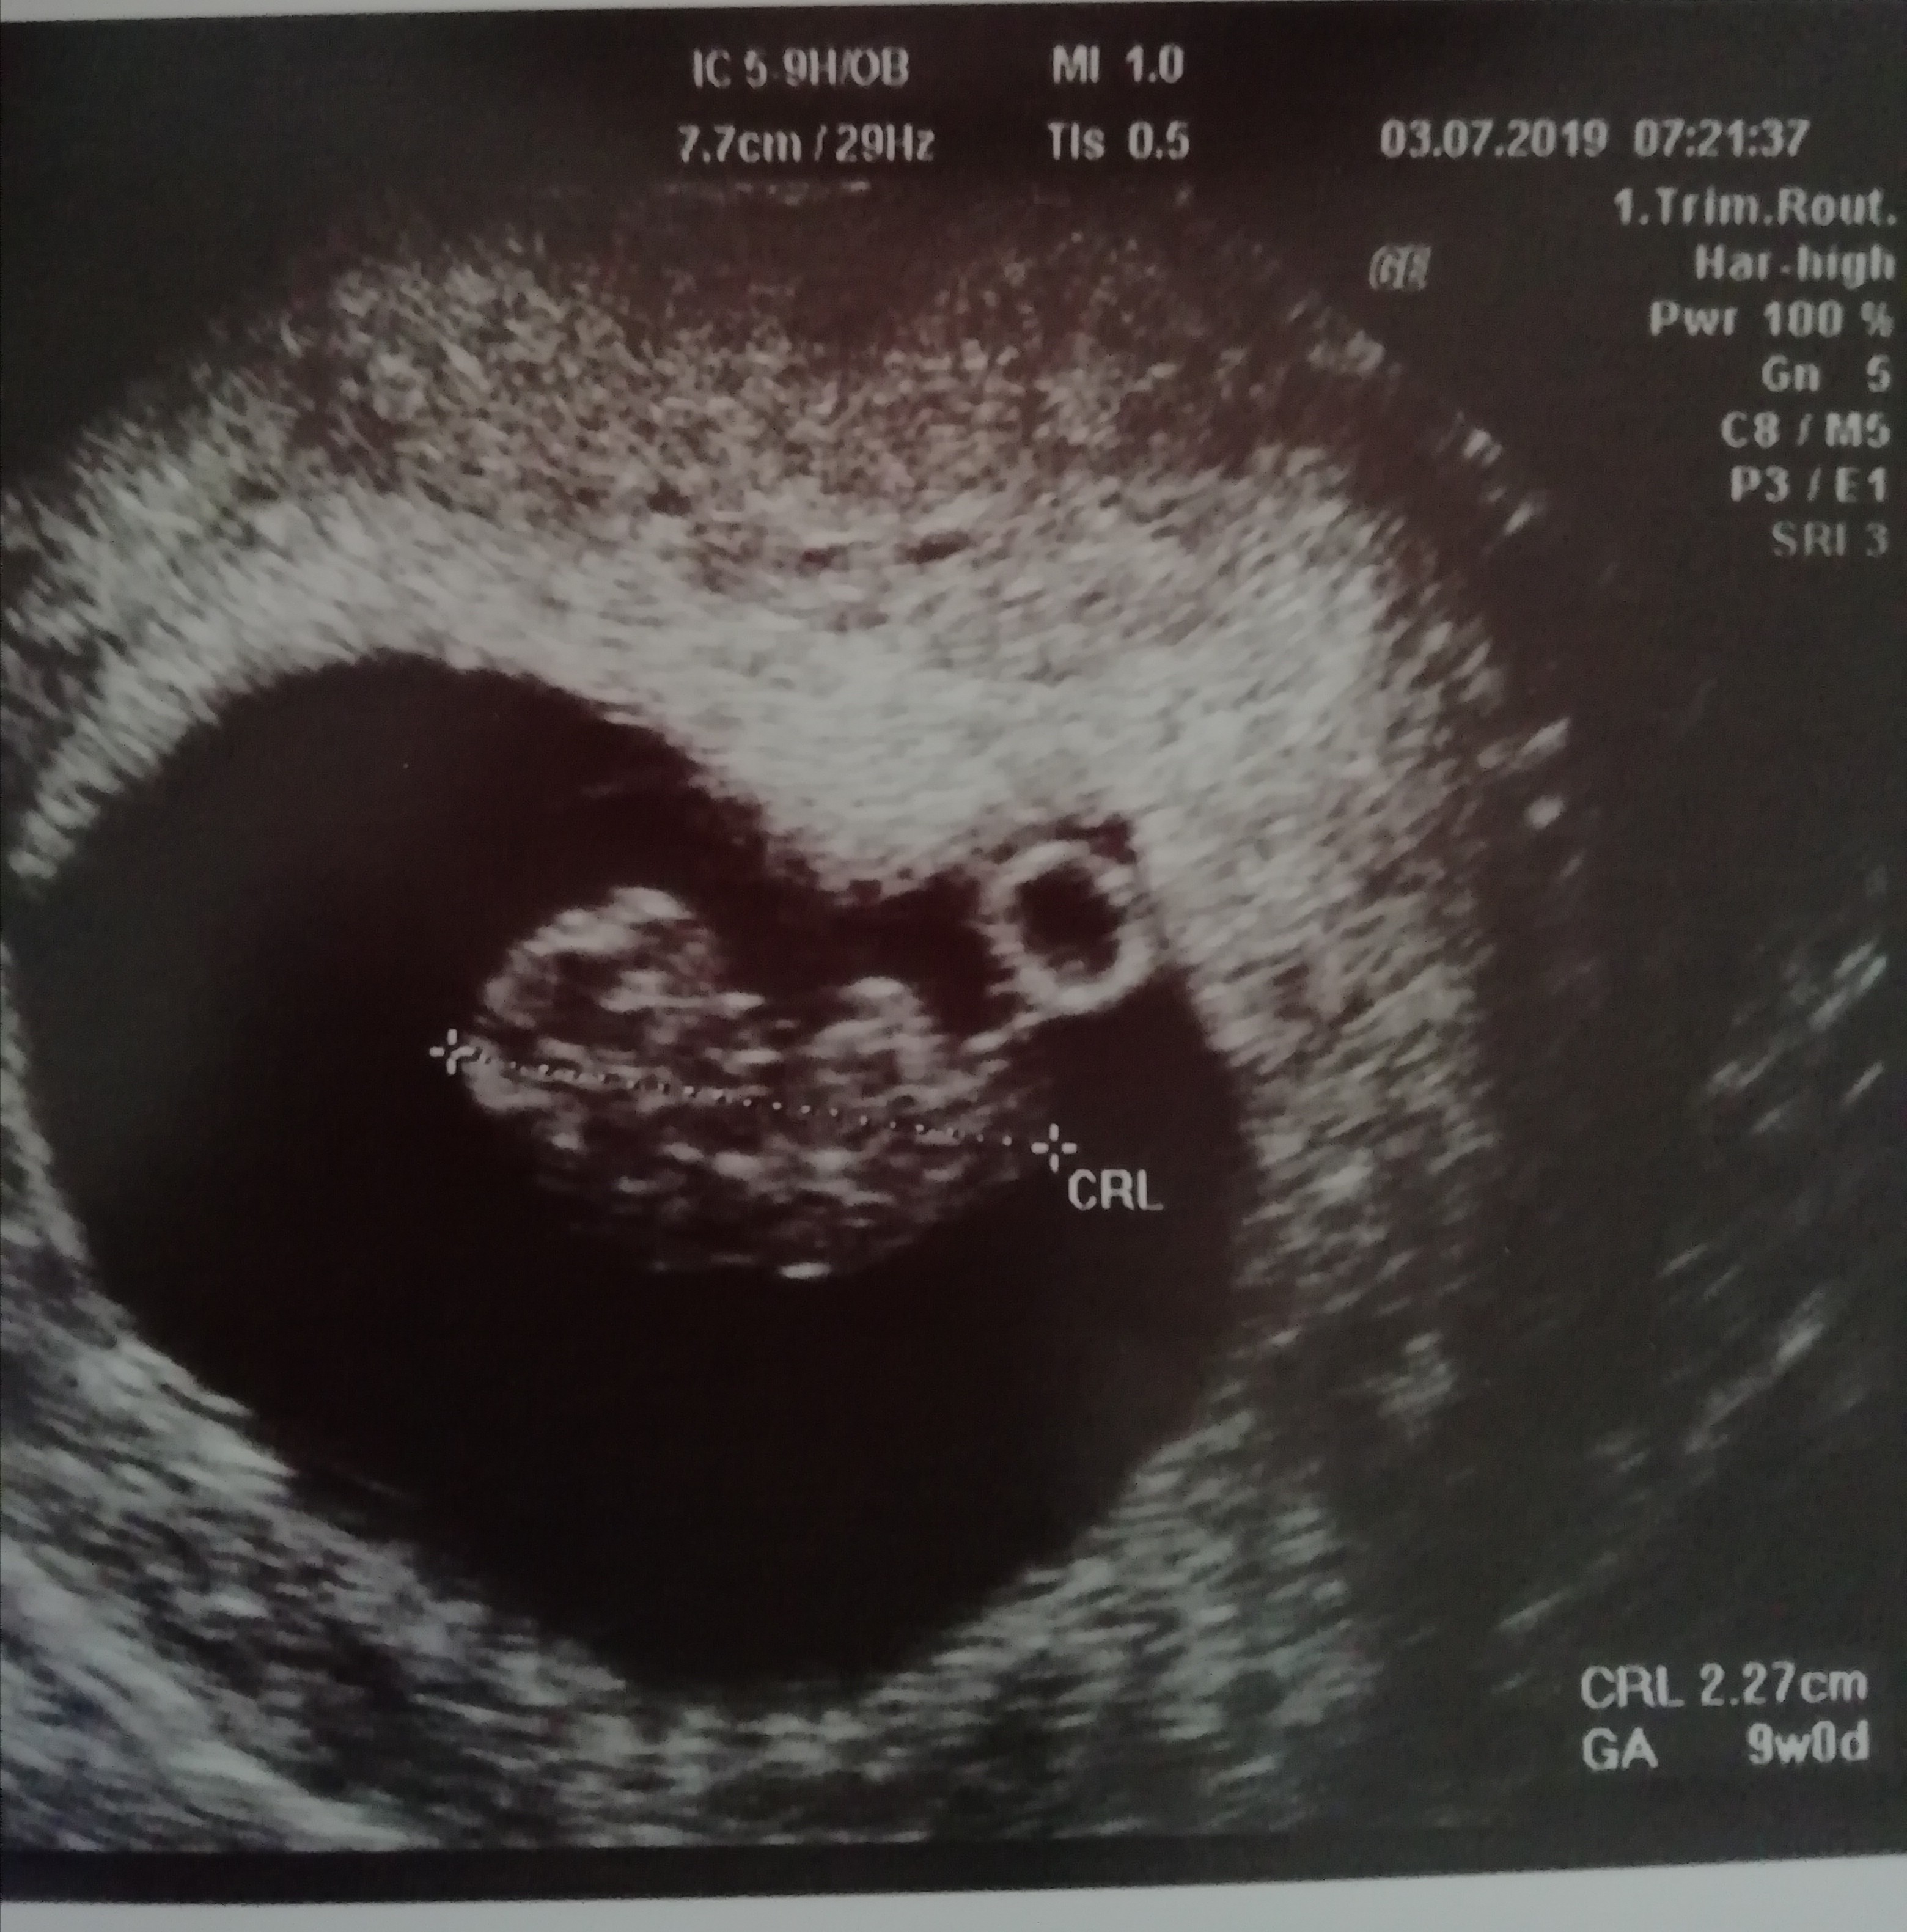

Dawaj fotę z usg [emoji16]

IMG_20190707_163329.jpg

Proszę :)